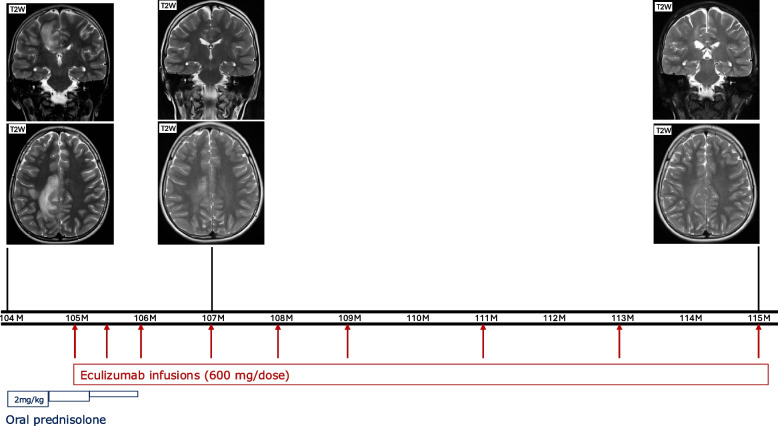

Results: Among the 49 patients, the mean age at initial presentation was 7.19 (± SD: 9.75) years. Most patients presented with infectious manifestations (n: 37, 75.5%), particularly sepsis (n: 18, 36.7%). The predominant pathogens were encapsulated organisms, particularly Neisseria meningitidis. Immune dysregulatory manifestations involved rheumatologic (n: 14, 28.57%), neurologic (n: 11, 22.4%), and renal (n: 8, 16.3%) disorders. Immunological evaluations showed low or absent levels of C3 and CFI in most patients. Genetic analysis identified 45 distinct mutations; less deleterious mutations, such as missense and splicing variants, were more common in those with immune dysregulation. Notably, three patients treated with eculizumab demonstrated significant clinical improvement.

Conclusion: Complete CFI deficiency presents a varied clinical spectrum, from asymptomatic to recurrent infections and immune dysregulation. Early diagnosis and targeted therapies, such as eculizumab, may improve patient outcomes. These findings underscore the necessity for further research into the nature of complete CFI deficiency and the development of optimal management strategies.